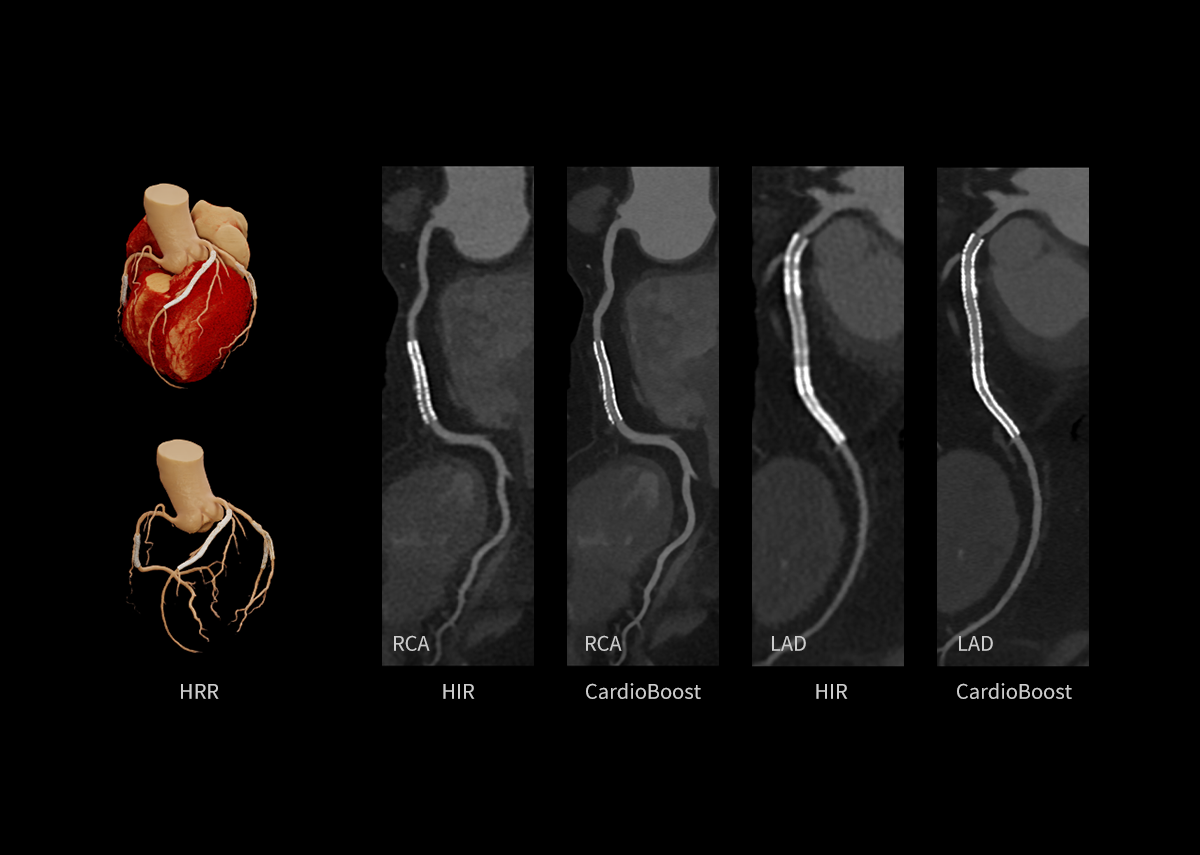

AIIR* – AI Iterative Reconstruction

Throughout the iterative loop of forward and backward projection between the raw data domain and the image domain, AIIR consistently takes into account the accurate modeling of optics, noise, anatomy, and physics statistics. Additionally, AIIR integrates deep learning-based de-noising technology, supplanting the conventional regularization role of MBIR in the optimization reconstruction process.

In brief, AIIR utilizes deep learning-based AI technology to attain robust noise reduction and natural image texture, while incorporating MBIR technology to achieve precise anatomical structure representation and artifact suppression. This technique surpasses the limitations of using either MBIR or deep learning reconstruction (DLR) independently.